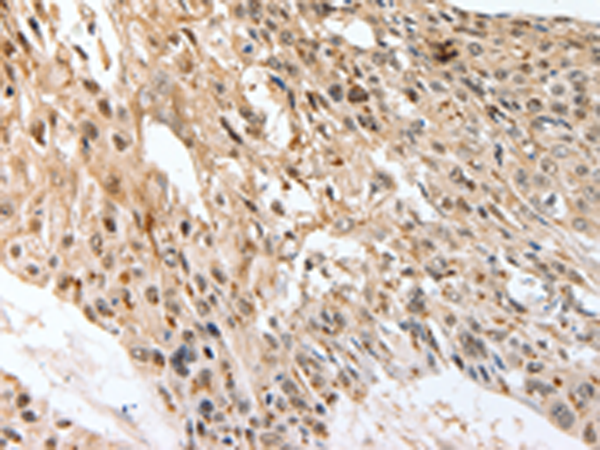

IHC positive control: |

Human esophagus cancer |

IHC Recommend dilution: |

50-200 |